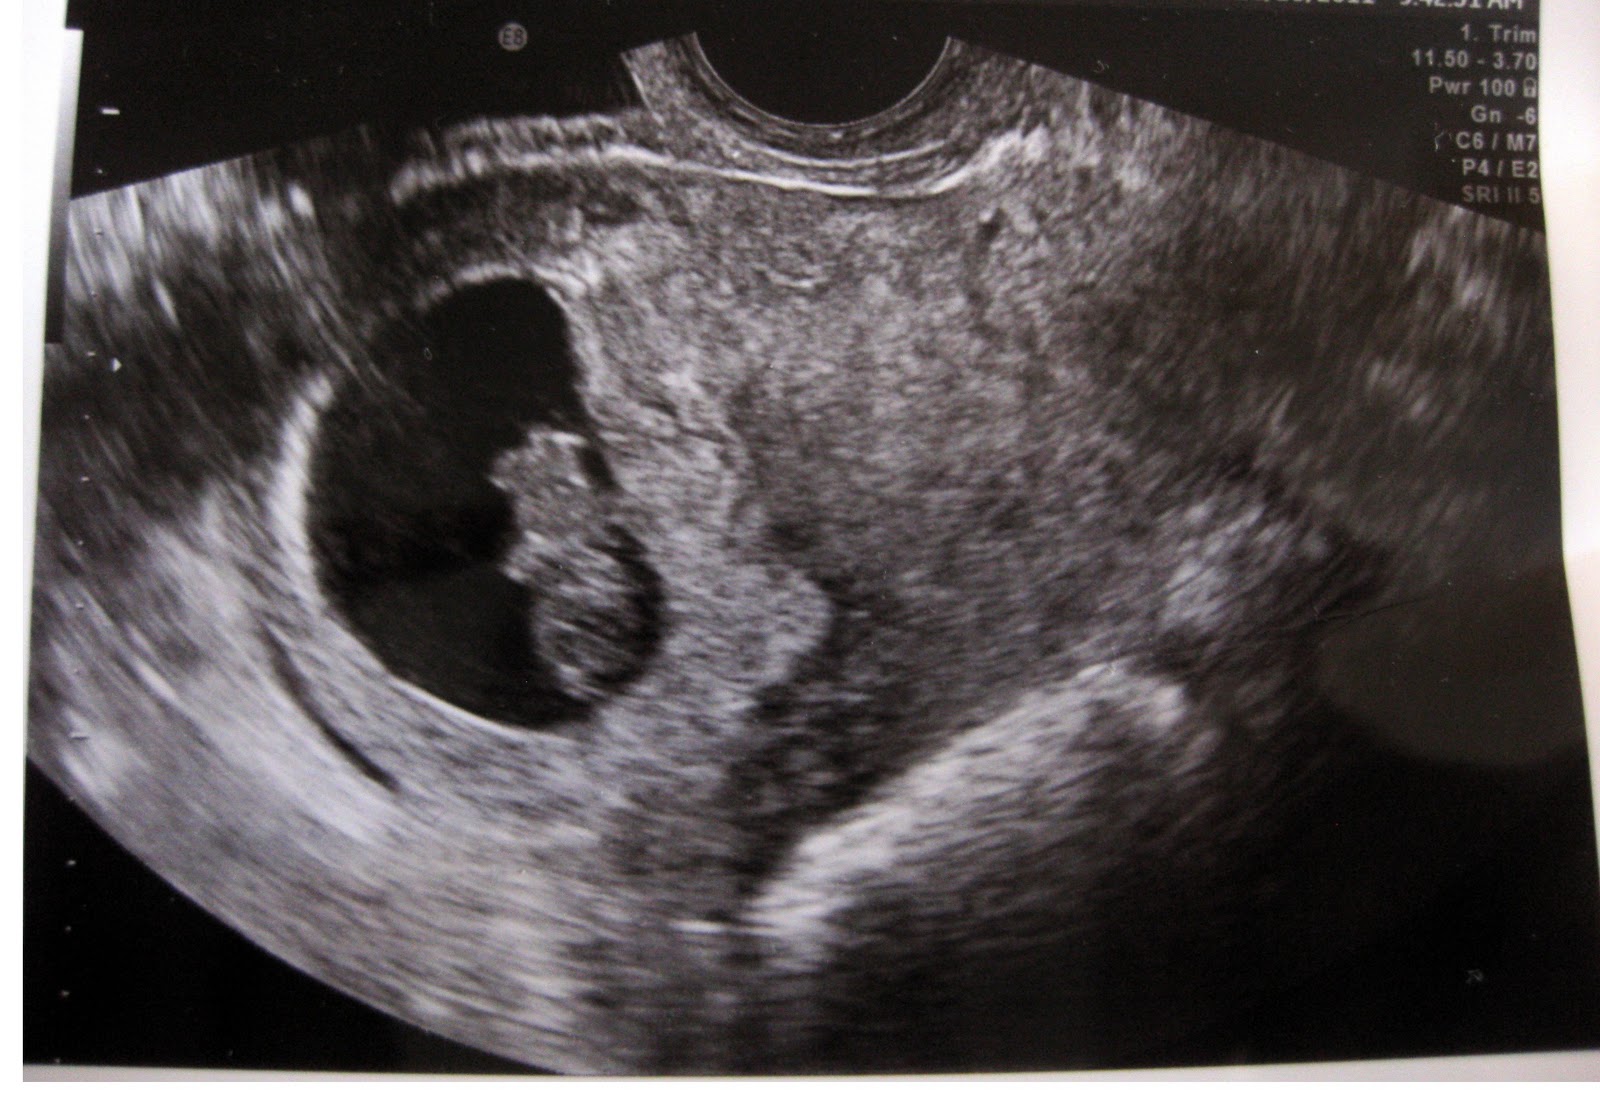

7 Акушерских Недель Фото

7 Акушерских Недель Фото 111 фотографий